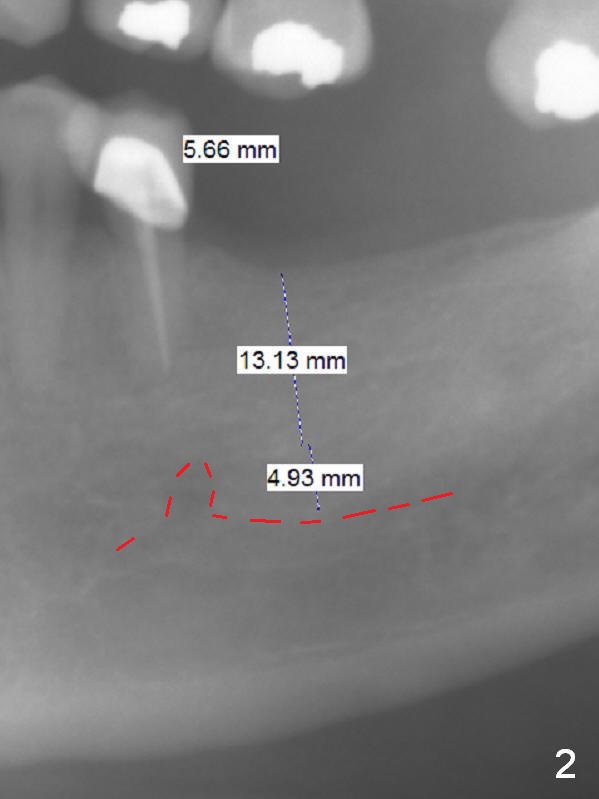

Early Loading for Intrusion A 66-year-old man has 3 missing teeth (Fig.1: #19,29,31) with supraerupted opposing teeth. Because of sufficient bone height (Fig.2: 13 mm (preferably 15 mm) fixture) and special fin pattern of IBS implant (stability), early loading (2 months, as opposed to 3 months in a previous case) is possible with a provisional to be placed at #19 to intrude the tooth #14. Start with Magic Split for access, bone density test and bone expansion if necessary. Place the implant deep. If primary stability is high, fabricate an immediate provisional with occlusal clearance. Reline the provisional for occlusal contact 2 months postop. Reline the provisional again so that it is able to intrude the tooth #14. Return to